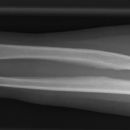

Unterarm total ventro-dorsal (1. Ebene a.-p.)

Technik

• FDA: 1.05 m

• Bildgröße: 20/43

• Übertischaufnahme

Indikation

Fraktur, Stellungskontrolle, Osteosynthesematerial

Lagerung

sitzend - seitlich zum Tisch

Arm ausgetreckt und Hand in Supination

Unterarm und Oberarm möglichst auf einer Höhe

Zentralstrahl

senkrecht auf Objektmitte

Einblendung

einschließlich Fingergrundgelenk und Ellenbogengelenk

Qualitätskriterien

Ulnar und Radius dürfen sich nicht überkreuzen (bei prox. UA). Ein Gelenk muss immer mit abgebildet sein.